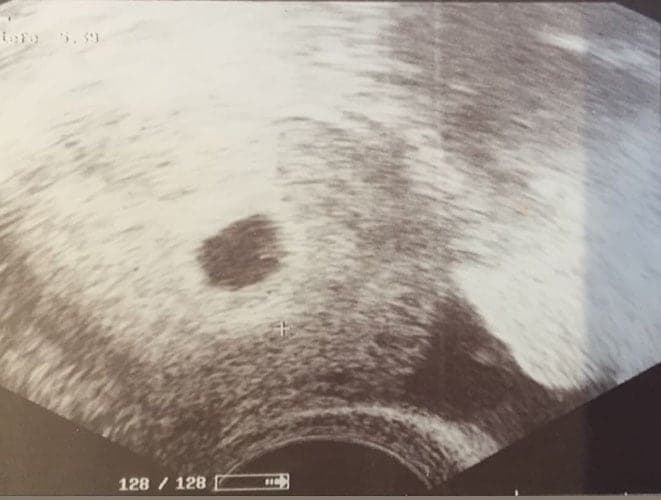

Ultraschallbilder aus dem 2. Trimester (13. bis 28. SSW)

Im 2. Trimester bekommt man oft die schönsten „Ganz-Körper“ Ultraschallbilder. Das Baby ist nun so groß, dass man alles gut erkennen kann und noch nicht zu groß, so dass es noch ganz auf das Bild passt. In dieser Zeit lässt sich meist das Geschlecht bestimmen, wobei manche Babys es einfach nicht preis geben wollen und sich immer so drehen, dass man nichts erkennen kann.